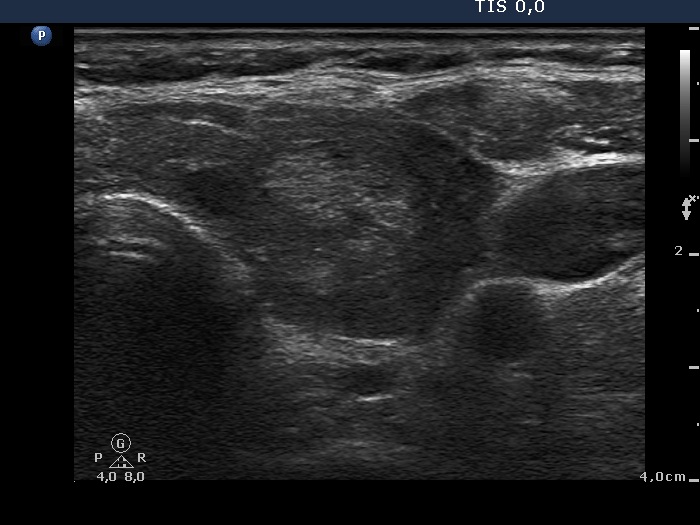

The shape of the nodule - case 1147 (ultrasonographic picture 5)

Lower part of the left lobe, transverse scan. There is another nodule showing a similar pattern to that demonstrated in the previous image.